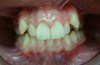

ÇAPRAZ KAPANIŞ

Üst ön dişler alt dişlerin gerisindedir. Çoğunlukla çene büyümesi kötü yönde etkilenir.